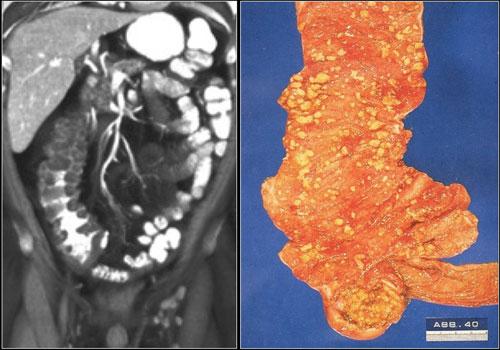

Đôi khi, tái tạo ảnh mặt phẳng coronal dạng lát cắt dày (thick slab coronal reconstructions) có thể hữu ích trong việc đánh giá mức độ ngấm thuốc.

Điều này được minh họa rõ ràng ở bệnh nhân này, trong đó hỗng tràng ngấm thuốc tốt (vùng xanh lá), trong khi hồi tràng giảm ngấm thuốc (vùng đỏ) do thiếu máu cục bộ.

Đây là một trường hợp tắc ruột quai kín khác.

Lưu ý sự khác biệt về mức độ ngấm thuốc giữa các quai ruột bình thường không giãn (mũi tên xanh lá) và các quai ruột giãn bị thắt nghẹt (mũi tên đỏ).

Ở trung tâm là các mạch máu mạc treo bị xoắn vặn (mũi tên vàng).